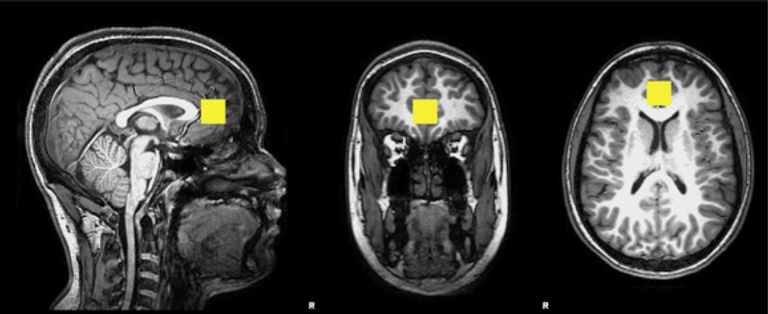

وخلال الدراسة فحص الباحثون مخ 145 طفلًا بمتوسط عمر 12 عامًا ، من خلال تقنية التصوير بالرنين المغناطيسي المتخصصة ، وذلك لتحديد مستويات الـ"ميو-إينوسيتول" الموجود في المخ، وهو مستقلب طبيعي يحدث بشكل أساسي في خلايا المخ المتخصصة المعروفة باسم "الخلايا الدبقية" ، والتي تساعد في الحفاظ على حجم الخلية وتوازن السوائل في الدماغ وتعمل كمنظمة للهرمونات والأنسولين في الجسم.

وترتبط الزيادات في مستويات الـ"ميو-إينوسيتول" بزيادة عدد الخلايا الدبقية ، والتي تحدث غالبًا في حالات الالتهاب.

ووجد الباحثون أنه من بين أولئك الذين تعرضوا لمستويات أعلى من التلوث، كانت هناك زيادات كبيرة في الـ"ميو-إينوسيتول" في المخ، مقارنة مع أولئك الذين تعرضوا لمستويات أقل.

كما لاحظوا أن الزيادة في الـ"ميو-إينوسيتول" تترافق مع أعراض القلق، حيث شهدت المجموعة الأكثر تعرضًا للتلوث، زيادة بنسبة 12% في أعراض القلق.